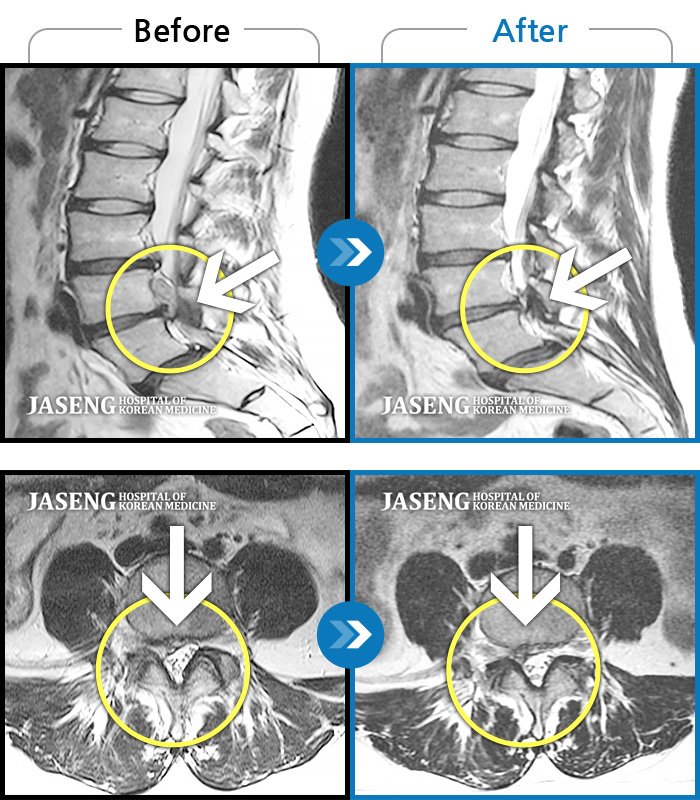

허리디스크

보라매 · 왕오호 원장

좌측 허리 통증과 좌측 다리 저림

촬영시기

2017.08.26 ~ 2018.08.21

2018.12.28